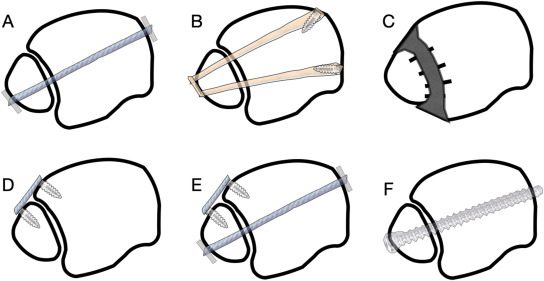

Методы фиксации

Рис. 21. Варианты фиксации межберцового синдесмоза

Описаны различные методы фиксации синдесмоза без единого консенсуса относительно оптимальной комбинации: один или два винта, винты 3,5 или 4,5 мм, металлические или биорезорбируемые винты, надсиндесмотическая или транссиндесмотическая установка, а также фиксация пуговичными фиксаторами (suture button).

Количество кортикалей при винтовой фиксации. Вопрос о том, сколько кортикалей должен захватывать позиционный винт, также остаётся дискуссионным. Биомеханические исследования и клинические данные не выявили значимых различий между трикортикальной и квадрикортикальной фиксацией ни по механической прочности, ни по функциональным результатам, ни по рентгенологическим параметрам. Трикортикальная фиксация рассматривается как адекватная альтернатива с сопоставимыми результатами.

Пуговичные фиксаторы vs. позиционные винты. Мета-анализ рандомизированных контролируемых исследований уровня I (Xu et al., 2023, SAGE Journals) показал, что пуговичные фиксаторы обеспечивают более высокий балл AOFAS через 3 месяца и 2 года, достоверно меньшую частоту подвывиха (0,8% vs 11,5%), поломки фиксатора (0% vs 25,4%) и необходимости удаления имплантата (6% vs 22,4%). На основании совокупности данных РКИ уровня I пуговичные фиксаторы получили рекомендацию уровня A (Xu et al., 2023). Это подтверждено более поздним мета-анализом (Archives of Orthopaedic and Trauma Surgery, 2024). Многоцентровое исследование Obey et al. (2024) также продемонстрировало достоверно более высокие баллы по шкале активности Tegner у пациентов после фиксации пуговичными фиксаторами.